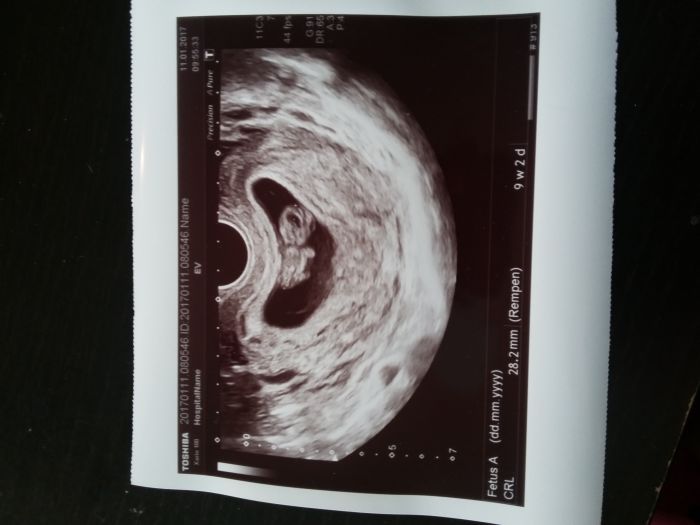

Ahoj holky, tak já byla dneska na kontrole 9+5 a všechno v pořádku, tak se mi šíleně ulevilo. Dostala jsem průkazku a taky se pochlubím fotečkou našeho malého ufounka